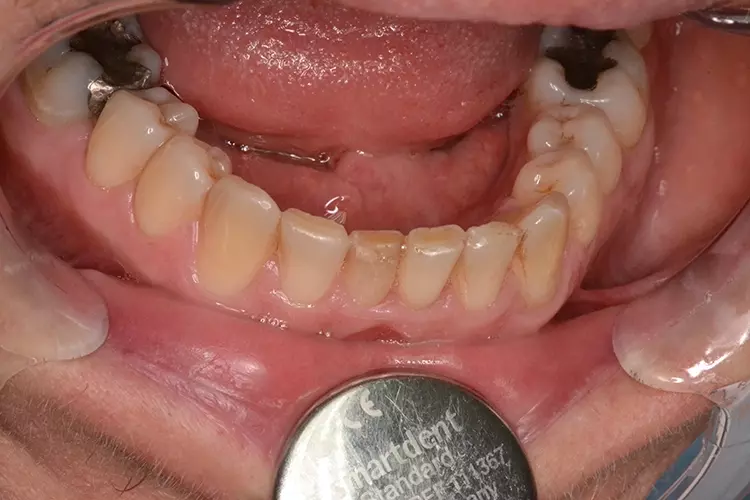

Bei dem heute 49-jährigen Patienten wurde seit Kindertagen versäumt, die Ober- und Unterkieferzahnbögen kieferorthopädisch auszurichten. Der Patient leidet seitdem stark unter seinen Zahnfehlstellungen.

Die Fraktur des stark elongierten Zahnes 21 war für den Patienten der Ausgangspunkt, sowohl die Front des Ober- als auch des Unterkiefers prothetisch überarbeiten zu lassen. Dabei wurde der frakturierte Zahn 21 durch ein navigiert eingesetztes Sofortimplantat ersetzt, während die verschachtelt stehenden Zähne 12 und 42 durch eine Brückenversorgung korrigiert wurden (Abb. 4a-j).